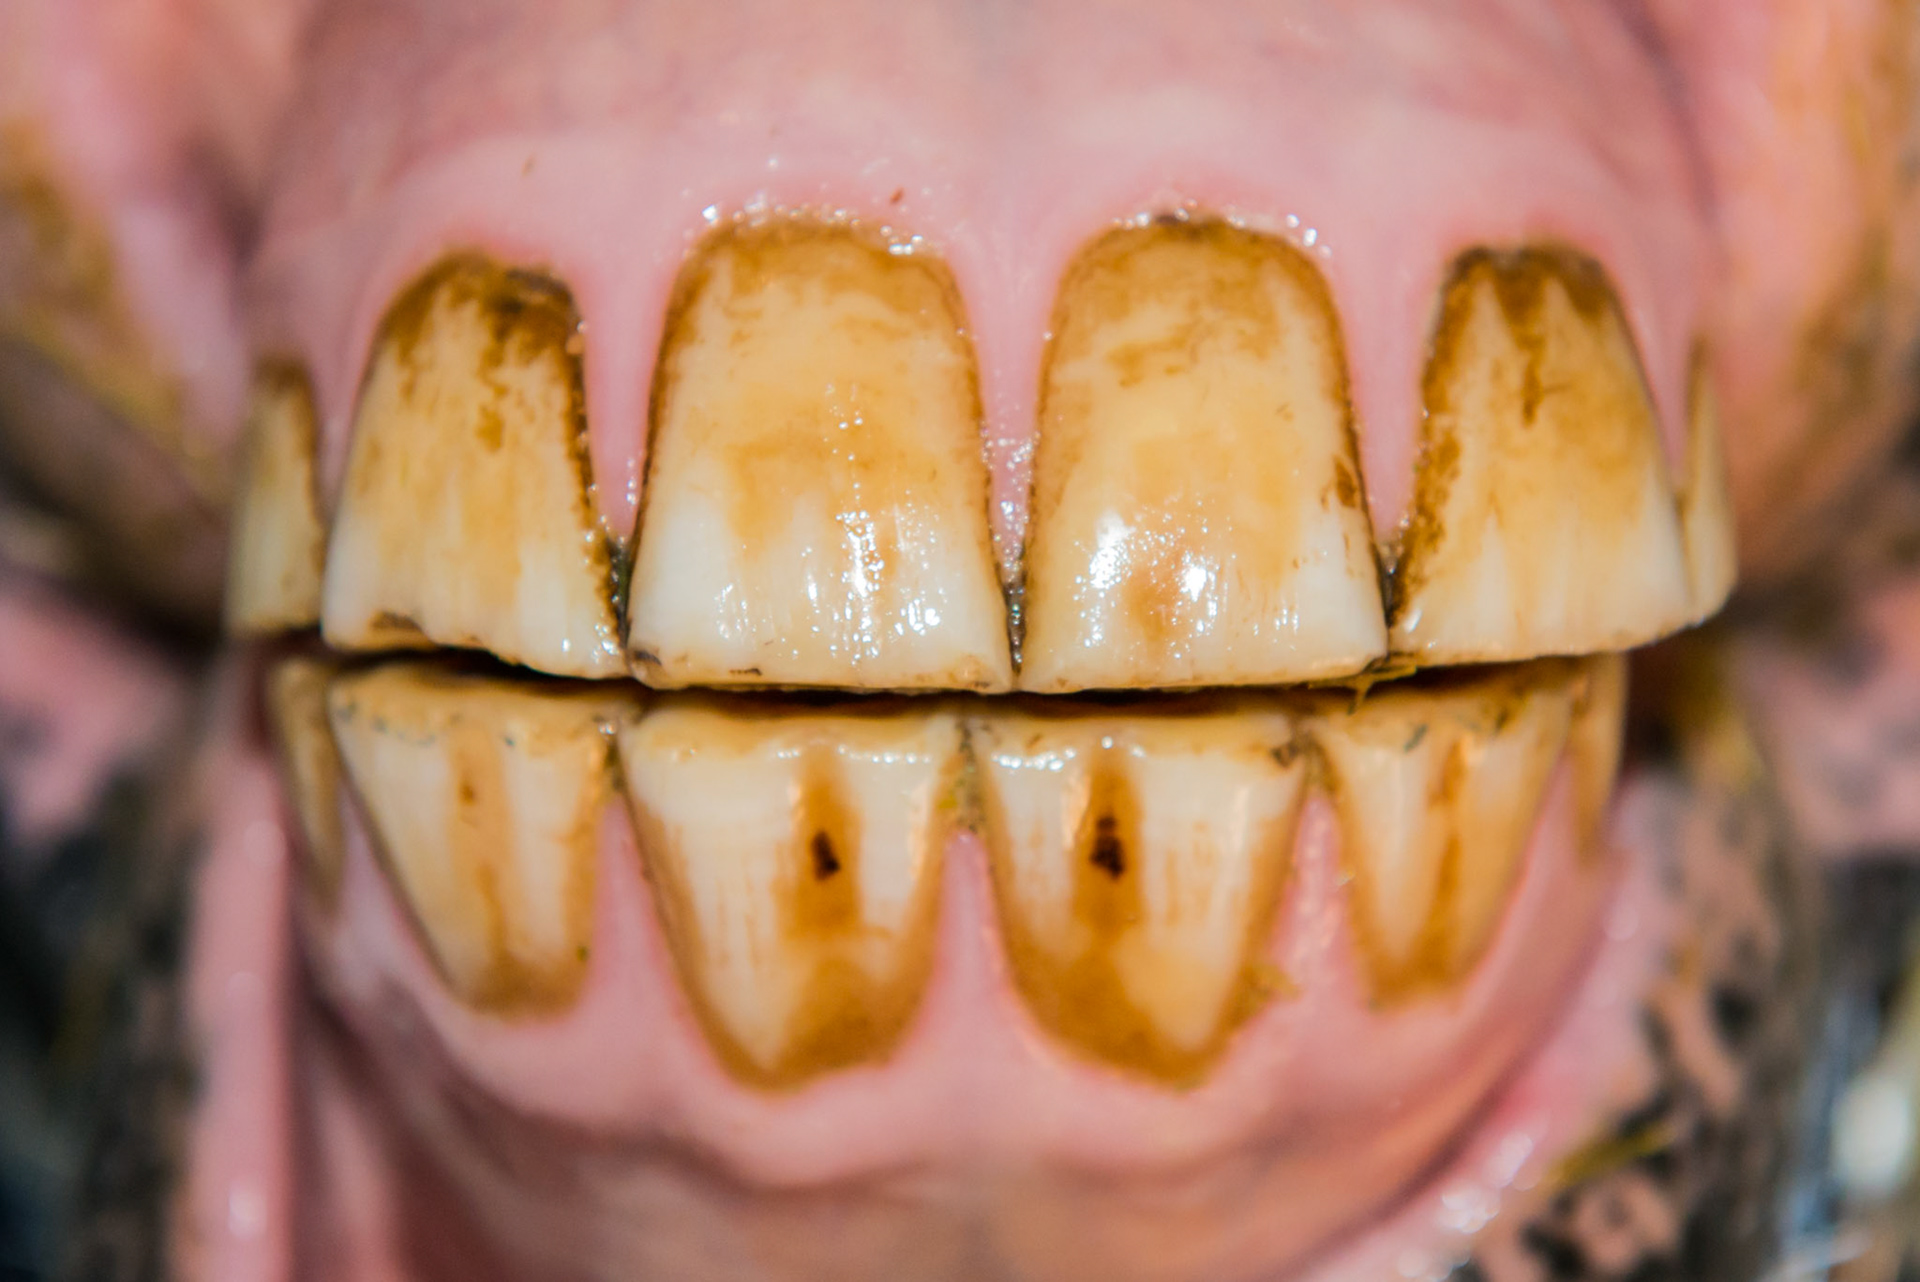

12yr 8mo note EOTRH